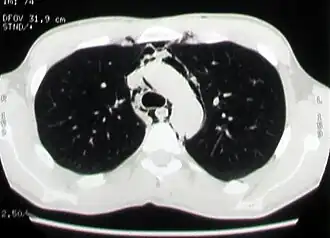

![]() КТ-изображение: эмфизема средостения у больного со спонтанным пневмомедиастинумом | |

Компьютерная томография органов грудной клетки

Компьютерная томография является наиболее эффективным методом диагностики эмфиземы средостения, так как с его помощью легко выявляется наличие газа в средостении, на поперечных сечениях хорошо определяется его локализация и распространённость эмфиземы. Преимуществом перед рентгенографией является возможность диагностики пневмомедиастинума даже в тех случаях, когда имеется выраженная эмфизема мягких тканей грудной стенки, сводящая информативность рентгенографии в этой ситуации к минимуму. Кроме того, компьютерная томография позволяет провести дифференциальную диагностику спонтанного пневмомедиастинума и других заболеваний с похожей клинической картиной, а также важна для установления причины заболевания[2][21].